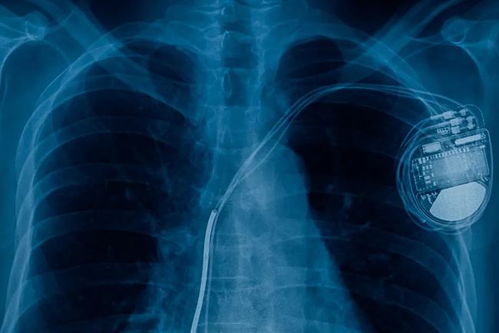

有些心跳加速可能是某些疾病的症状。如心血管疾病,冠心病、心力衰竭等心脏问题会导致心脏代偿性加速。心律失常,如房颤、室上速,可能引发突发心悸。代谢异常,如甲亢患者因甲状腺激素过量会持续心率增快,贫血时心脏需加速泵血补偿缺氧。感染或发热也会导致心率增快。某些药物,特别是感冒药、平喘药或激素类药物,也可能引起心率加快。